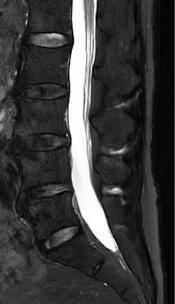

• 不同入路脊柱内镜手术治疗L4/5节段脱垂型腰椎间盘突出症的疗效比较

2025, 31(7):76-85. DOI: 10.12235/E20240433

摘要 (95) HTML (94) PDF 1.13 M (100) 评论 (0) 收藏

摘要:目的 观察经椎间孔入路内镜下腰椎间盘切除术(TELD)和经椎板间入路内镜下腰椎间盘摘除术(IELD)治疗L4/5节段脱垂型腰椎间盘突出症(LDH)的临床疗效。方法 回顾性分析2020年11月-2022年11月该院采用脊柱内镜手术治疗的75例L4/5节段脱垂型LDH患者的临床资料。根据手术入路的不同,将患者分为TELD组(53例)和IELD组(22例)。比较两组患者的手术情况和术后疗效。结果 与TELD组比较,IELD组的手术时间明显缩短,术中透视次数明显减少,差异均有统计学意义(P < 0.05);两组患者住院时间和并发症发生率比较,差异均无统计学意义(P > 0.05)。所有患者术后均获得12~19个月的随访。两组患者末次随访时的视觉模拟评分法(VAS)评分和Oswestry功能障碍指数(ODI)明显低于术前,且IELD组明显低于TELD组,差异均有统计学意义(P < 0.05)。按照突出物和神经根的不同位置进一步分析,两组肩上型患者(TELD组10例,IELD组6例)末次随访时的VAS评分和ODI明显低于术前,且IELD组末次随访时的VAS评分明显低于TELD组,差异均有统计学意义(P < 0.05);两组腋下型患者(TELD组8例,IELD组16例)末次随访时的VAS评分和ODI明显低于术前,且IELD组明显低于TELD组,差异均有统计学意义(P < 0.05);35例肩前型患者经TELD术后,末次随访时的VAS评分和ODI明显低于术前,差异有统计学意义(P < 0.05)。按照突出物的不同Lee分区进一步分析,两组Lee Ⅲ区患者(TELD组44例,IELD组10例)末次随访时的VAS评分和ODI明显低于术前,且IELD组的ODI明显低于TELD组,差异均有统计学意义(P < 0.05);两组Lee Ⅳ区患者(TELD组9例,IELD组12例)末次随访时的VAS评分和ODI明显低于术前,且IELD组明显低于TELD组,差异均有统计学意义(P < 0.05)。结论 采用TELD和IELD治疗L4/5节段脱垂型LDH,均可获得较满意的减压效果,但IELD的手术时间相对较短,X线透视次数较少,且对肩上型、腋下型、Lee Ⅲ区和Lee Ⅳ区的减压效果更有优势。